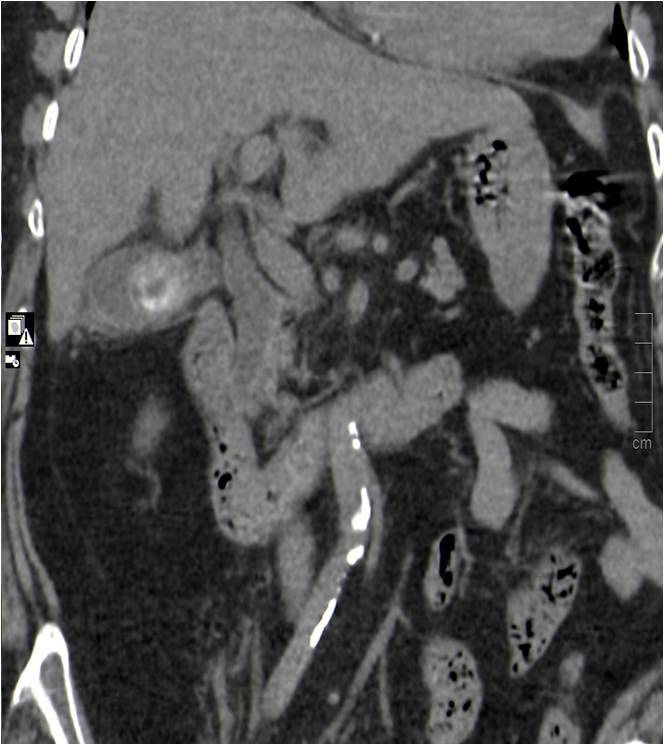

El TC abdominal nos ofrece una gran visión sobre las estructuras anatómicas y la capacidad de discernir diferentes órganos y es una técnica no invasiva.